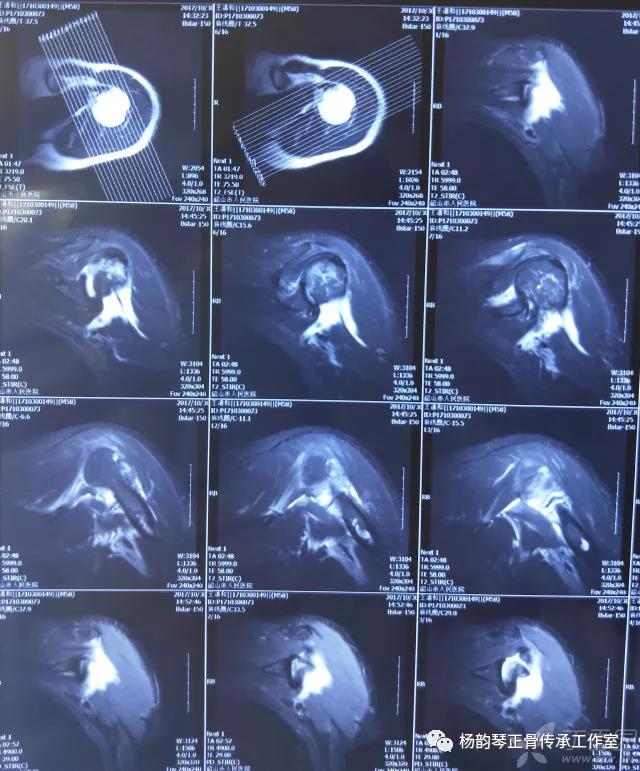

简要病史:骑摩托车跌倒致左肩部肿痛,活动受限,就诊于当地医院,拍片及磁共振检查后诊断为肩袖损伤及肩关节半脱位,予以悬吊固定,因症状缓解不明显就诊于我院。外院拍片情况如下:

应该说是一个典型的“灯泡征”影像,但是并未引起注意。

当地接诊医生应该说还是很负责的,同时拍了健侧片对比:

影像科报告,骨科医生光看报告行吗?